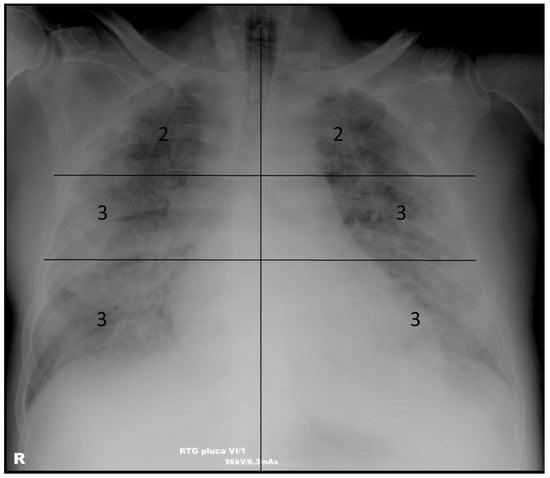

2.4. Scoring System